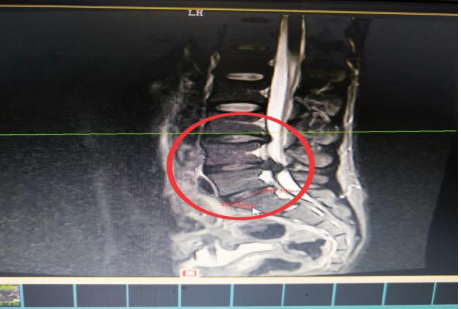

10分鐘后,患者肖先生沒有家屬陪同的情況下被緊急到骨科一區(qū)病房。接診滿頭大汗、非常緊張肖先生,舒小林醫(yī)師仔細(xì)詢問了病情。原來肖先生從事搬運行業(yè),半年前就腰腿痛就醫(yī),當(dāng)時在保守治療后稍有緩解,沒有引起重視直到11月13日下午因搬重物后突然感到腰腿劇烈疼痛、麻木、大小便困難,這才120急救電話。骨科一區(qū)錢軍副主任舒小林醫(yī)師立即給患者作了詳細(xì)的體查,并立即聯(lián)系做急診腰椎磁共振確定有無神經(jīng)受壓。腰椎磁共振結(jié)果提示:腰4/腰5椎間盤膨出,導(dǎo)致馬尾神經(jīng)嚴(yán)重受壓,有明顯的手術(shù)指征,如不盡快手術(shù)會致神經(jīng)受損難以恢復(fù)。錢軍副主任來到肖先生病床前,將手術(shù)方案、手術(shù)風(fēng)險及并發(fā)癥詳細(xì)告知肖先生本人,肖先生表示同意并簽字馬上手術(shù)。